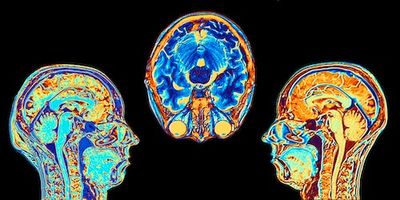

The Latest Breaking News from Brain